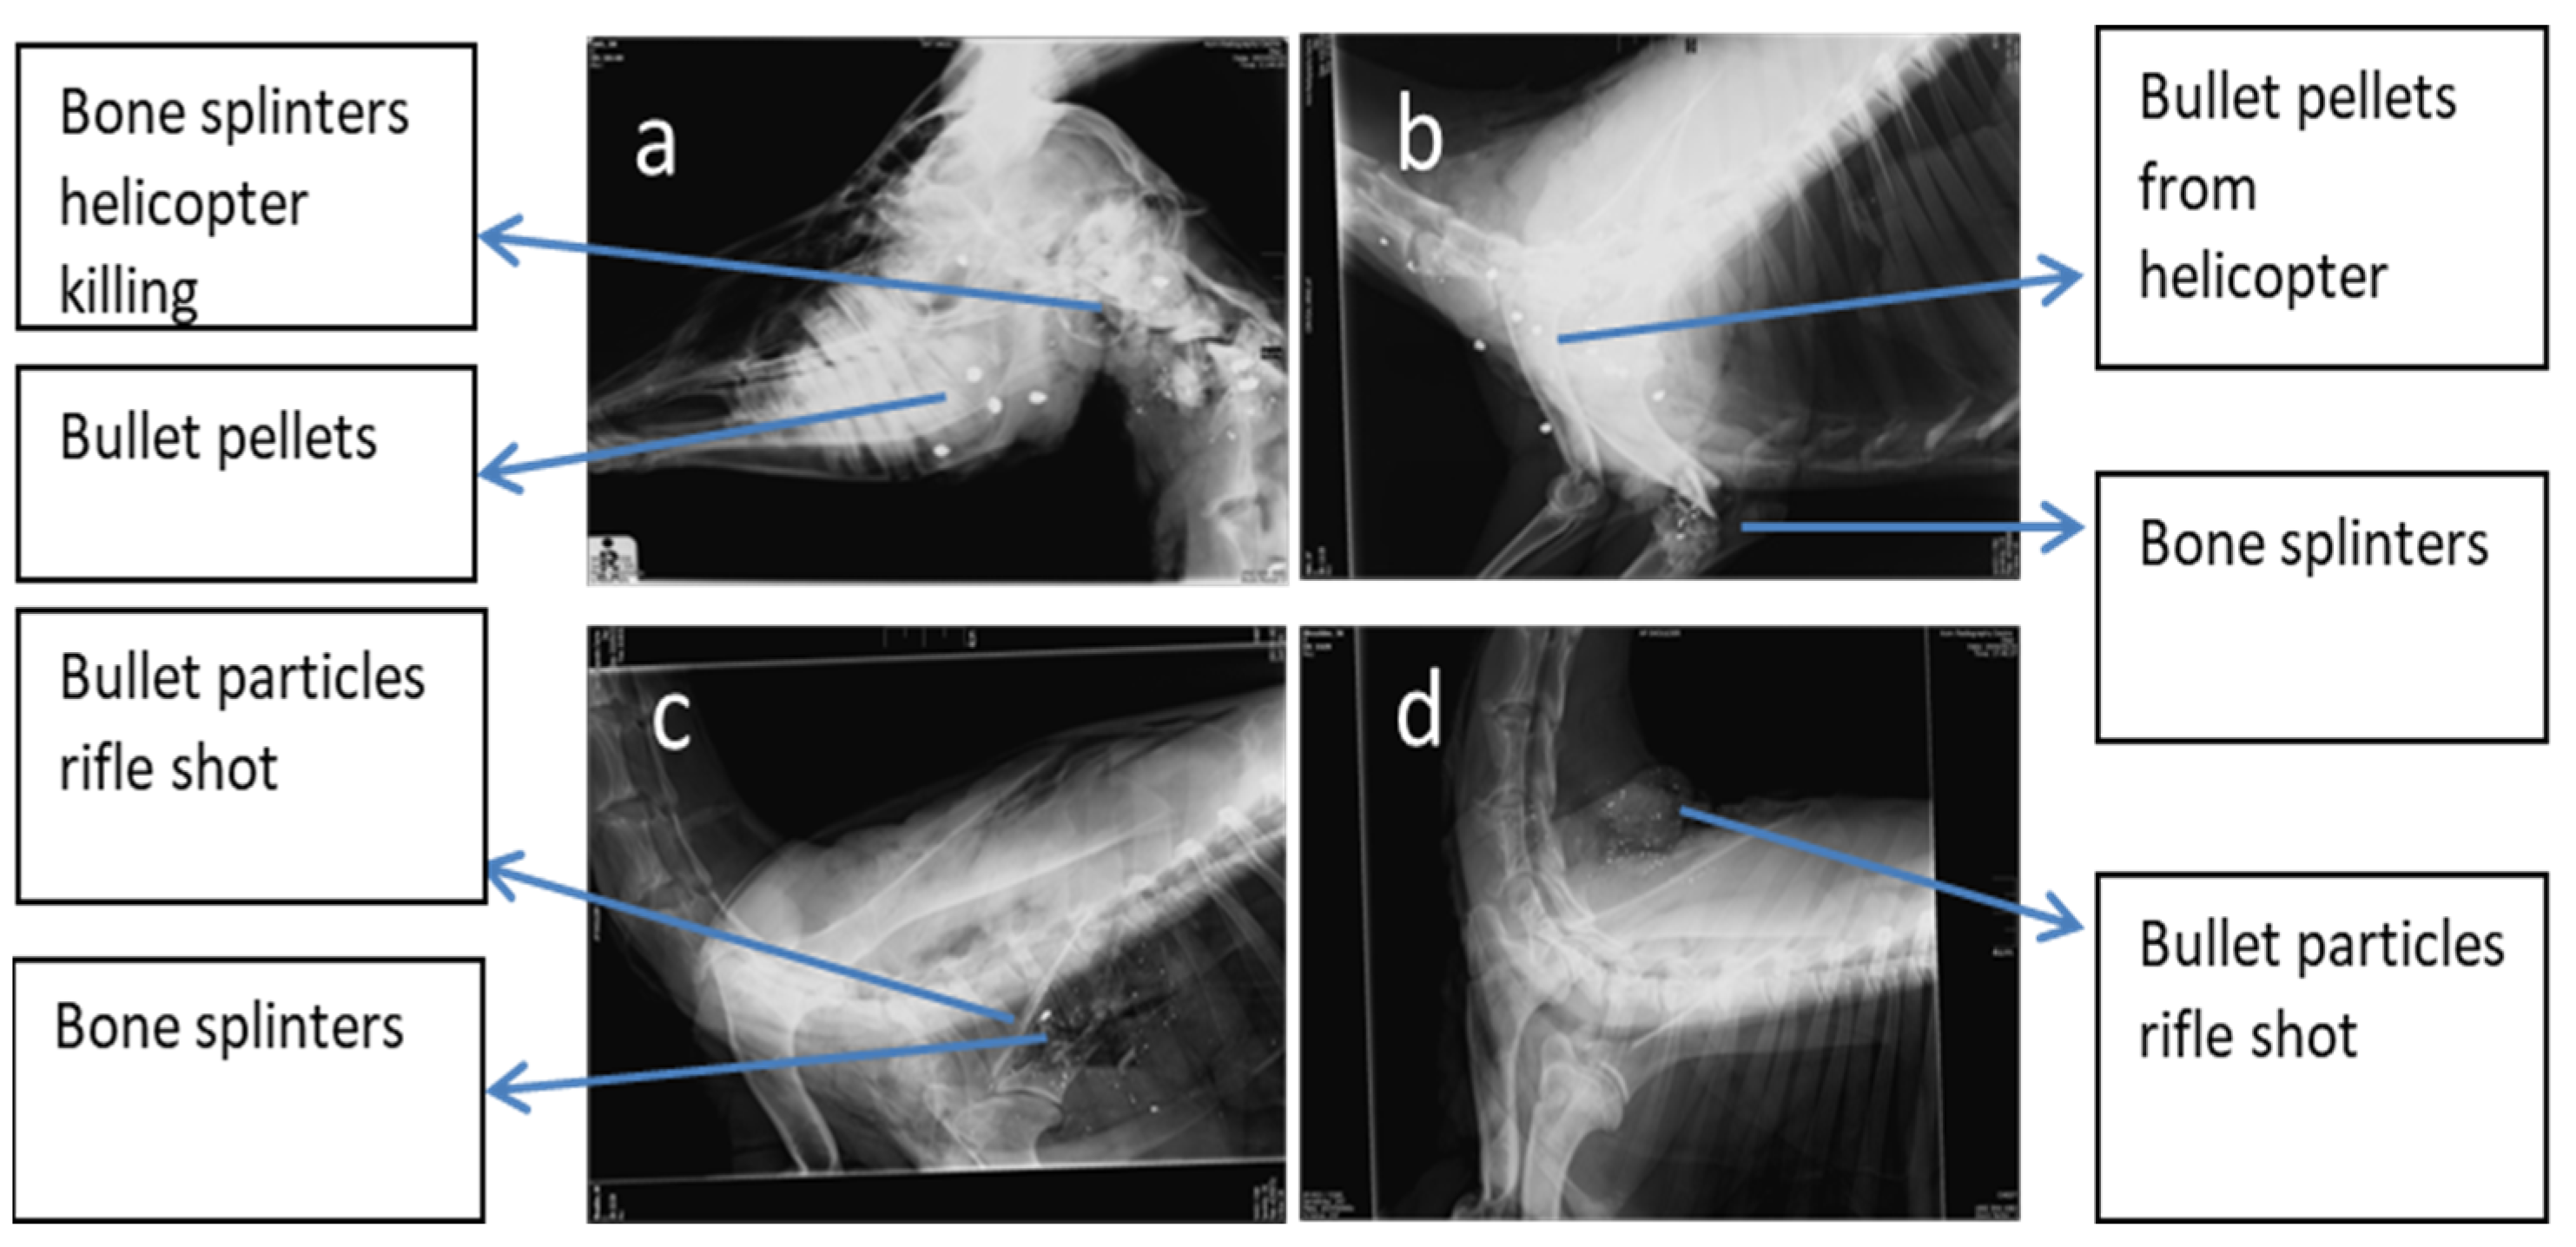

3.1. Impact and Dispersion of Physical Hazards

3.2. Particle Sizes of Bone Splinters and Bullet Fragments